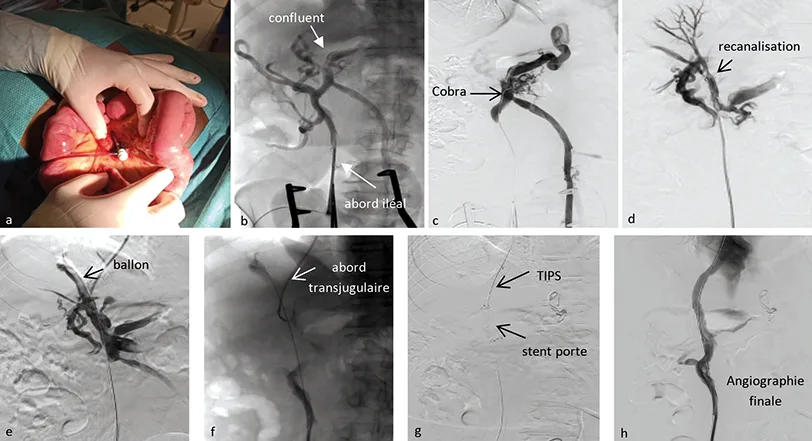

Figure 3 : Exemple de recanalisation portale d’un cavernome par voie transmésentérique

a) Mise en place d’un introducteur dans une veine iléale par abord mésentérique ;

b) Opacification du réseau mésentérique depuis l’introducteur iléal qui permet de repérer le confluent splénomésaraïque ;

c) Sonde Cobra amenée en regard du confluent splénomésaraïque ;

d) Recanalisation du réseau porte jusqu’en intrahépatique ;

e) Dilatation au ballon de la branche portale droite ;

f) Ponction de la branche droite reperméabilisée depuis l’abord transjugulaire ;

g) Insertion d’un stent porte en amont du TIPS ;

h) Angiographie finale confirmant la reperméabilisation.

Un exemple de recanalisation portale par voie transmésentérique est présenté sur la figure 3.